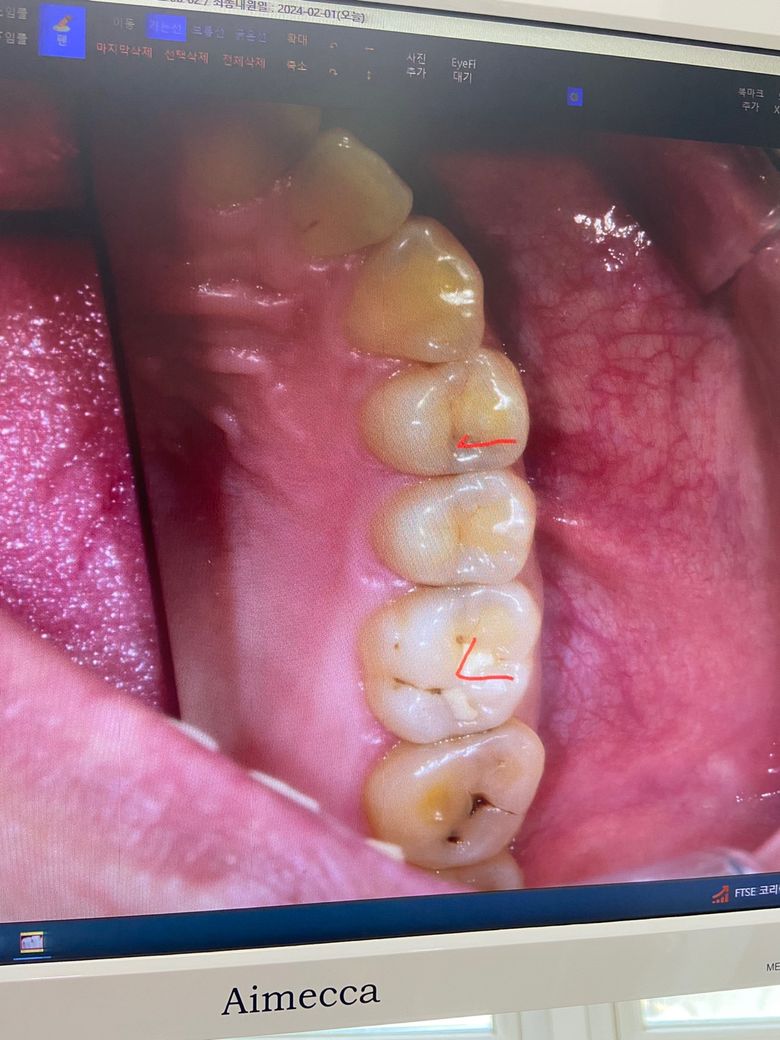

해당 사진에서 (우측 최하단 사랑니는 오늘 발치했습니다)

V 표기한 치아를 인레이 해야하고

V좌측의 두개의 치아는 레진으로 치료해야한다고 합니다.

제1대구치 (6번째 치아)의 경우 기존 떼우는 치료를 했는데도 추가적으로 충치(이차충치)가 생긴 것을 감안하여 인레이 치료를 하자고 하신 것 같습니다.

제1소구치(4번째 치아)에서도 충치는 어느정도 있는 것으로 보이며 인레이가 아니라 레진으로 가능한 범주라면 레진으로 치료하면 됩니다.

제2소구치(5번째 치아)의 경우 충치가 의심되나 방사선 사진을 찍어 확인해봐야 하고

제2대구치(7번째 치아) 씹는면에도 약간의 초기 충치가 확인됩니다.